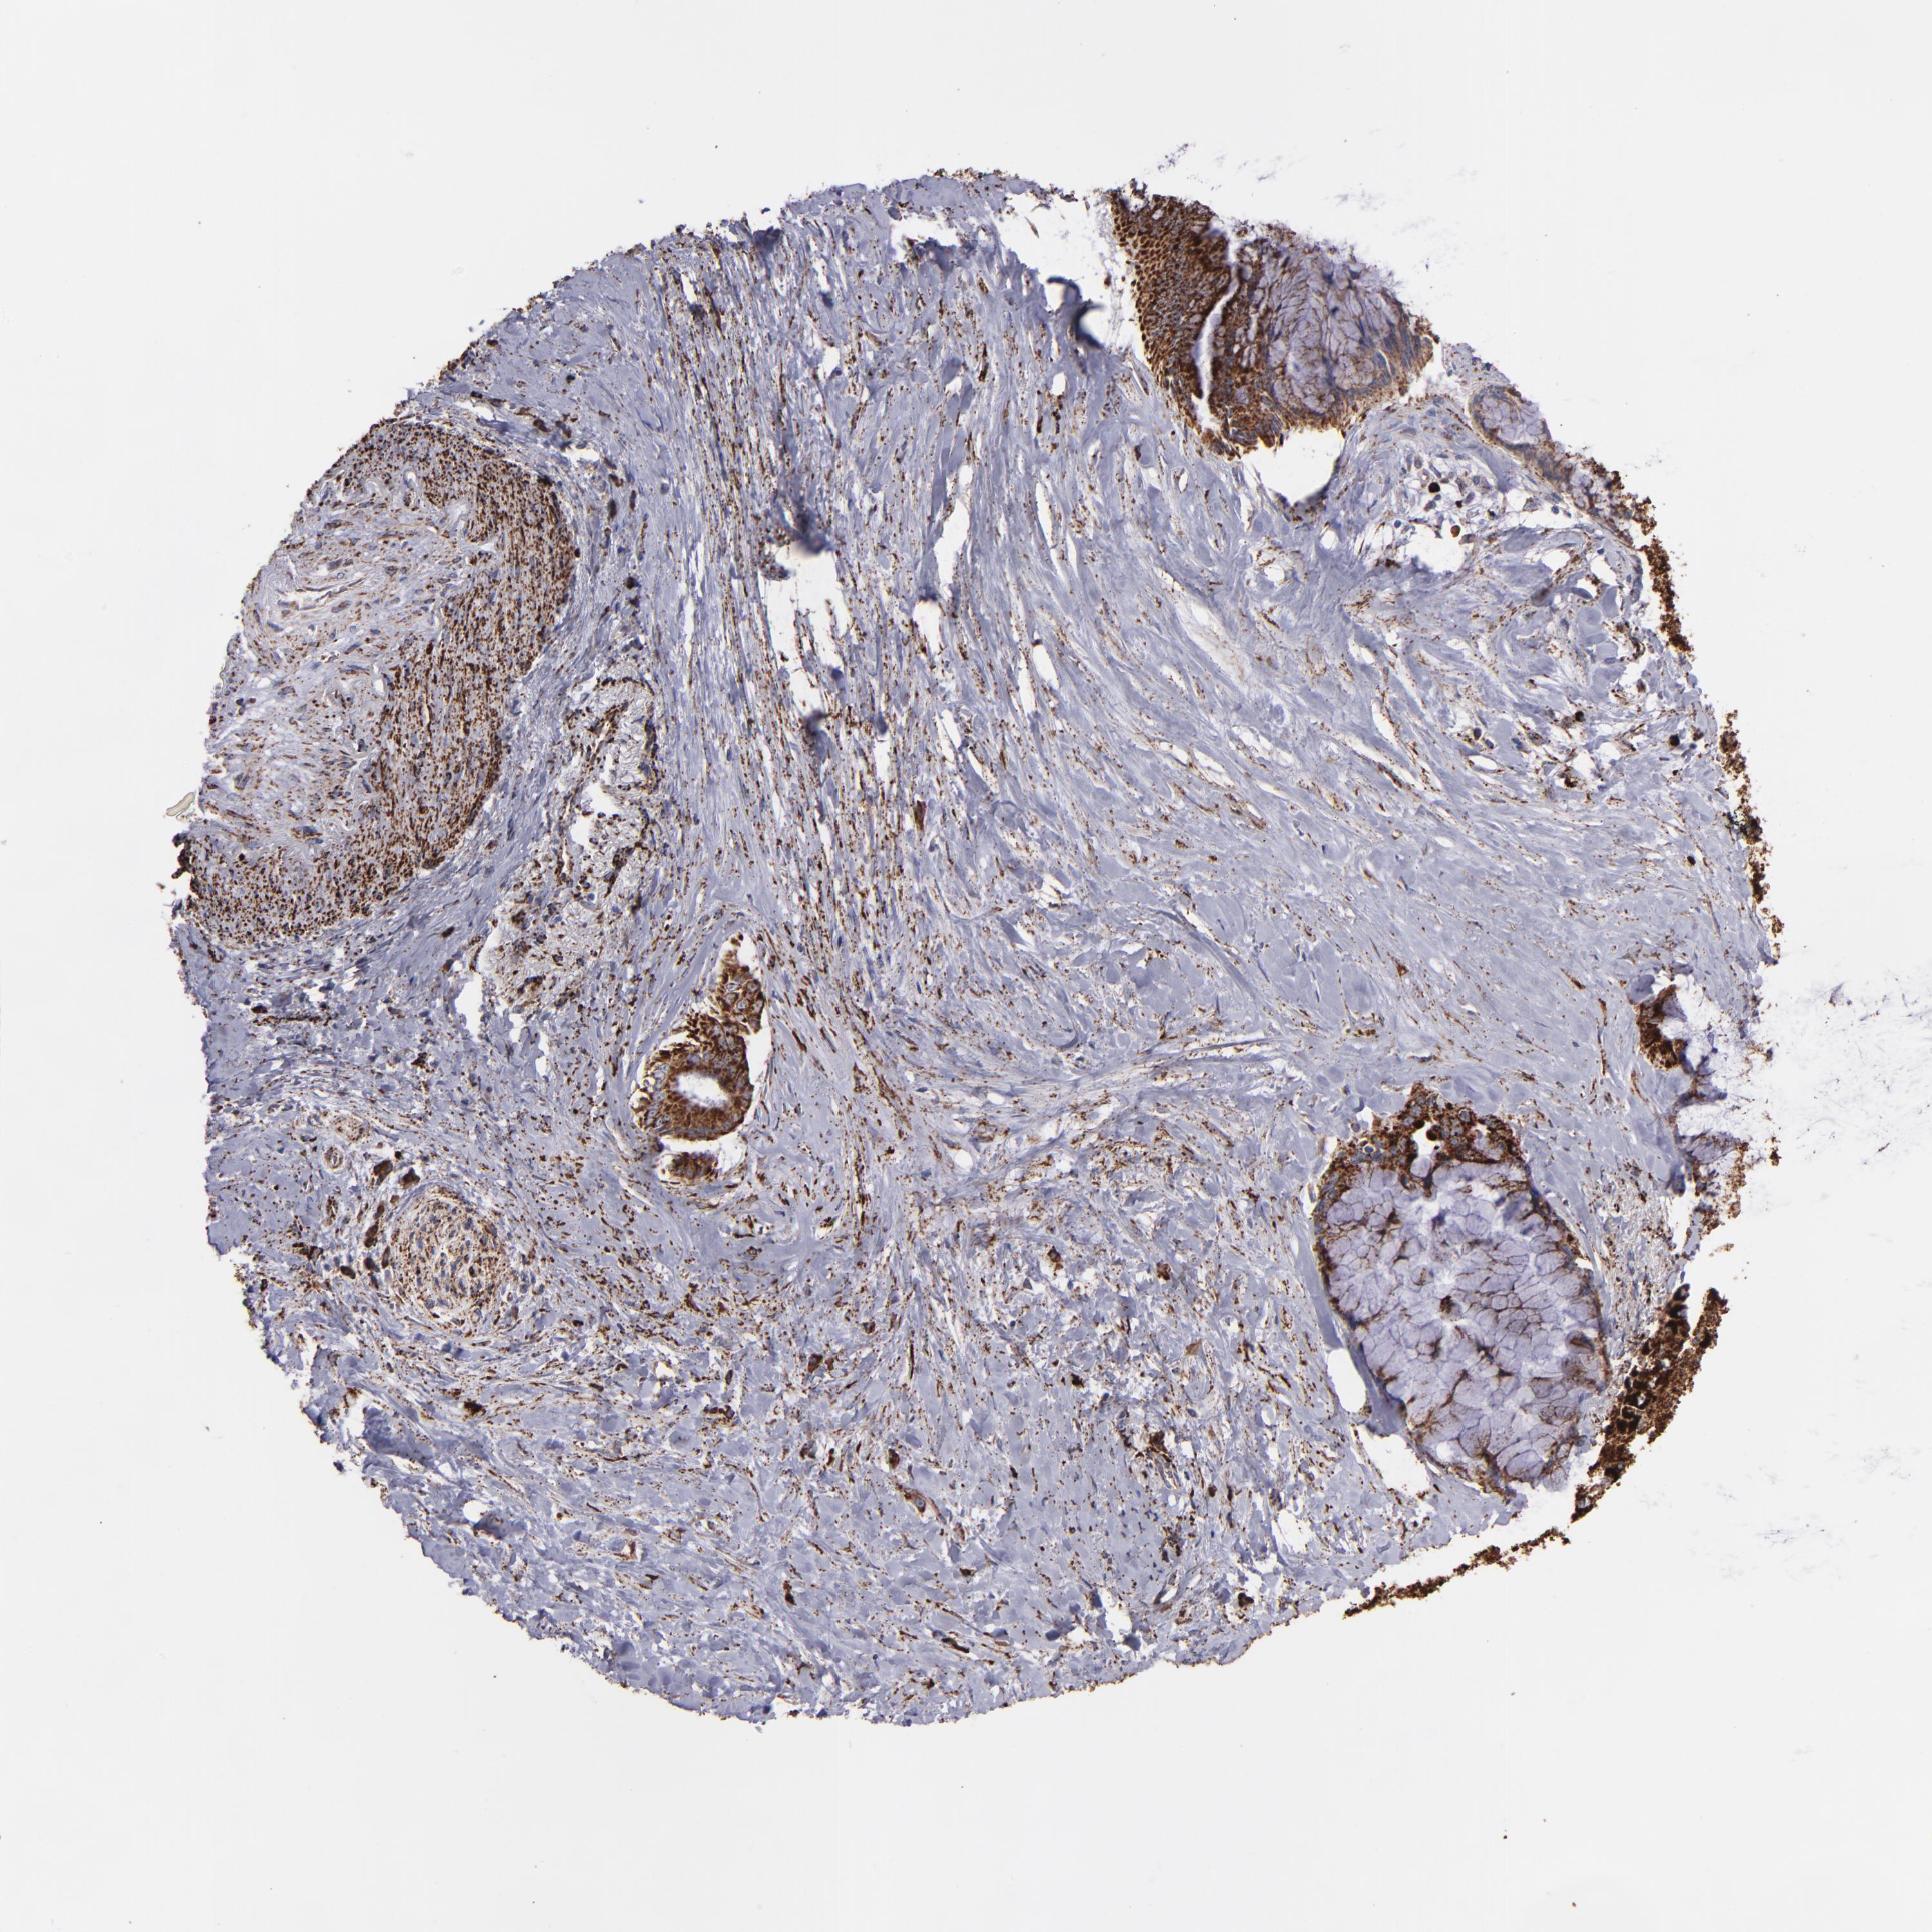

PANCREATIC CANCER - Protein expressioni

A mouse-over function shows sample information and annotation data. Click on an image to view it in a full screen mode. Samples can be filtered based on level of antibody staining by selecting one or several of the following categories: high, medium, low and not detected. The assay and annotation is described here.

Note that samples used for immunohistochemistry by the Human Protein Atlas do not correspond to samples in the TCGA dataset.

Antibody stainingi

Antibody staining in the annotated cell types in the current human tissue is reported as not detected, low, medium, or high, based on conventional immunohistochemistry profiling in selected tissues. This score is based on the combination of the staining intensity and fraction of stained cells.

Each image is clickable and will lead to virtual microscopy that enables deeper exploration of all samples and also displays staining intensity scores, fraction scores and subcellular localization as well as patient and tissue information for each sample.

Antibody HPA002328

Antibody CAB037200

Staining

High

Medium

Low

Not detected

Intensity

Strong

Moderate

Weak

Negative

Quantity

>75%

75%-25%

<25%

None

Location

Nuclear

Cytoplasmic/membranous

Cytoplasmic/membranous,nuclear

Adenocarcinoma, NOS